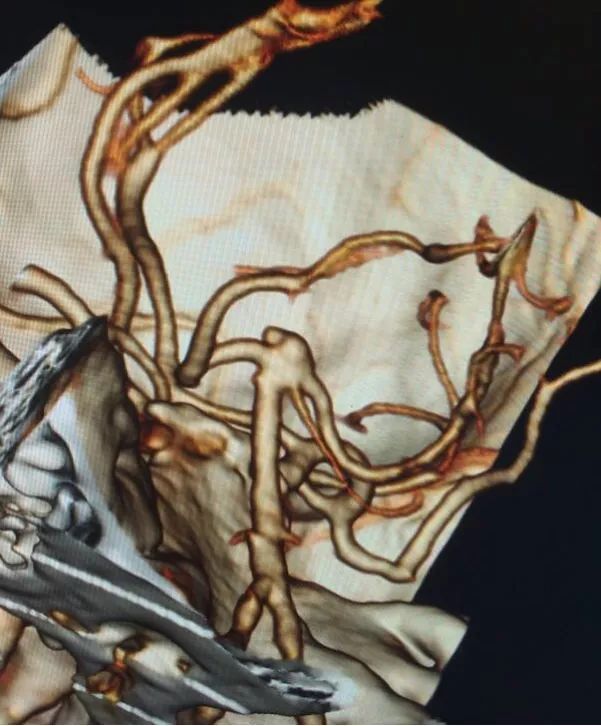

左椎动脉造影三维重建和测量